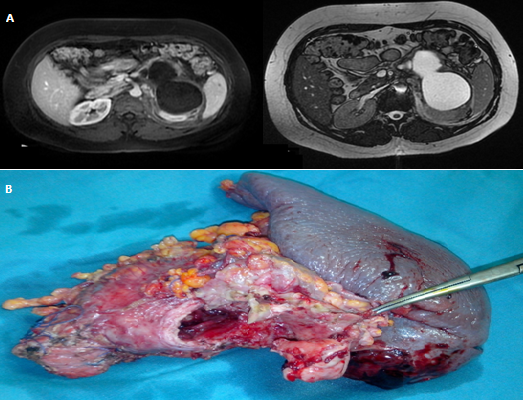

Les cystadénomes mucineux sont des tumeurs bénignes à potentiel malin. Ils sont souvent révélés par des douleurs abdominales non spécifiques, un ictère, ou un épisode de pancréatite aiguë. Nous rapportons l’observation exceptionnelle d’un cystadénome mucineux doublement compliqué de pancréatite aigue et de rupture dans le rétro-péritoine. Il s’agit d’une patiente âgée de 30 ans, non tarée, qui nous a consulté pour des douleurs épigastriques et de l’hypochondre gauche évoluant depuis trois mois et qui se sont accentuées depuis 3 jours, sans fièvre ni ictère. L’examen clinique avait noté un empâtement à la palpation de l’épigastre et de l’hypochondre gauche. Il n’y avait pas de masse palpable. Le bilan biologique était sans anomalie en dehors d'une lipasémie à 8 fois la normale. Une TDM abdominale a été pratiquée montrant une masse kystique de la queue du pancréas, bi-loculée de 111 mm x 73 mm, à paroi fine et à contenu liquidien, associé à une infiltration du fascia para rénal gauche. Un complément d’IRM (A) a été réalisé montrant un aspect de cystadénome mucineux rompu dans rétro-péritoine. La portion caudale du canal pancréatique principal était légèrement dilatée et communiquait avec le kyste pancréatique. La malade a été opérée par voie bi sous costale. Il s’agissait d’une formation kystique de la queue du pancréas rompue dans le rétro-péritoine associée à une pancréatite aigue (coulée de nécrose de l’espace pré rénal antérieur gauche). Il a alors été réalisé une splénopancréatectomie caudale (B). Les suites opératoires ont été simples. L’examen anatomo-pathologique de la pièce opératoire avait conclu à un cystadénome mucineux pancréatique siège de lésions de dysplasie de bas grade.